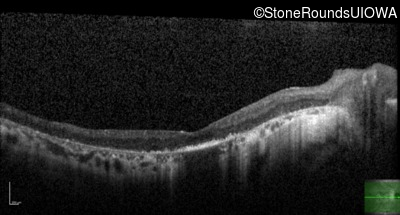

Visit at age: 38 years

Optical Coherence Tomography - Right - 20/70

Exemplar / OCT Stack